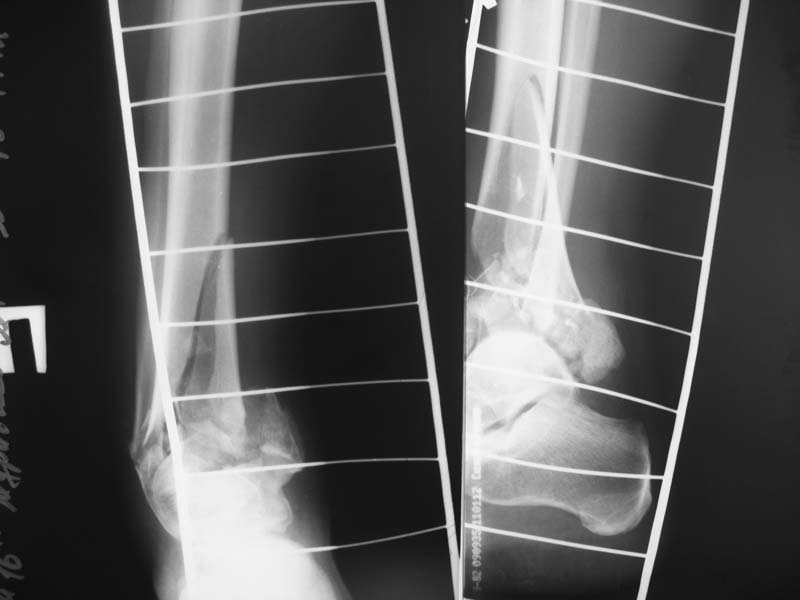

Здравствуйте, уважаемые коллеги. Помогите определиться с тактикой лечения. В отделение

поступил пациент с тяжелым закрытым переломом дистального отдела костей голени (см.

рентгенограммы), травма получена в результате падения с высоты 2-го этажа. Пациенту 38 лет.

Состояние пациента удовлетворительное, кожные покровы голени в удовлетворительном

состоянии. Вопрос: как вы считаете, какую тактику предпочтительнее выбрать в данном случае

- первичное артродезирование или попытаться выполнить реконструкцию суставной

поверхности большеберцовой кости. Очень важны ваши комментарии. Если есть